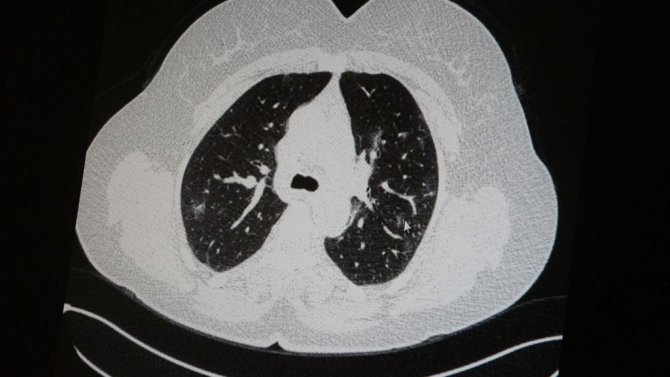

Elazığ'da öksürük, halsizlik, yorgunluk ve çabuk yorulma gibi şikayetlerle hastaneye başvuran ve korona virüs tespit edilen 2 genç hastadan aşısız olanının tomografi sonuçlarında virüsün akciğerlerde zatürreye sebebiyet verdiği görüldü. Aynı şekilde aşı olup korona virüs hastalığına yakalanan bir başka genç hastanın bilgisayarlı akciğer tomografisinde akciğerinde herhangi bir sorunun olmadığı belirlendi.

Medical Park Elazığ Hastanesi Göğüs Hastalıkları Uzmanı Dr. Cebrail Azar, geçtiğimiz yıla oranla yoğun bakımda yatan hastaların yaş ortalamasının 65'ten 35'lere kadar düştüğüne dikkat çekti. Genç olduğu halde aşı olmayanlarda hastalığın ağır seyrettiğini ifade eden Uzm. Dr. Azar, "Ben gencim, benim bağışıklık sistemim kuvvetli" diyen genç bir hastanın akciğerlerinde ciddi lekelenmelerin olduğunu ve korona virüs zatürresi olduğunu gördüklerini belitti. Uzm. Dr. Azar, aynı şekilde aşı olup korona virüs hastalığına yakalanan bir başka genç hastanın akciğer tomografisinde akciğerde herhangi bir sorunun olmadığını ve hastanın durumunun iyi olduğunu gözlemlediklerini kaydetti. Uzm. Dr. Azar, sürekli şahit oldukları "Keşke biz aşı olsaydık" sözünü bir daha duymamak için herkesi aşı olmaya davet etti.